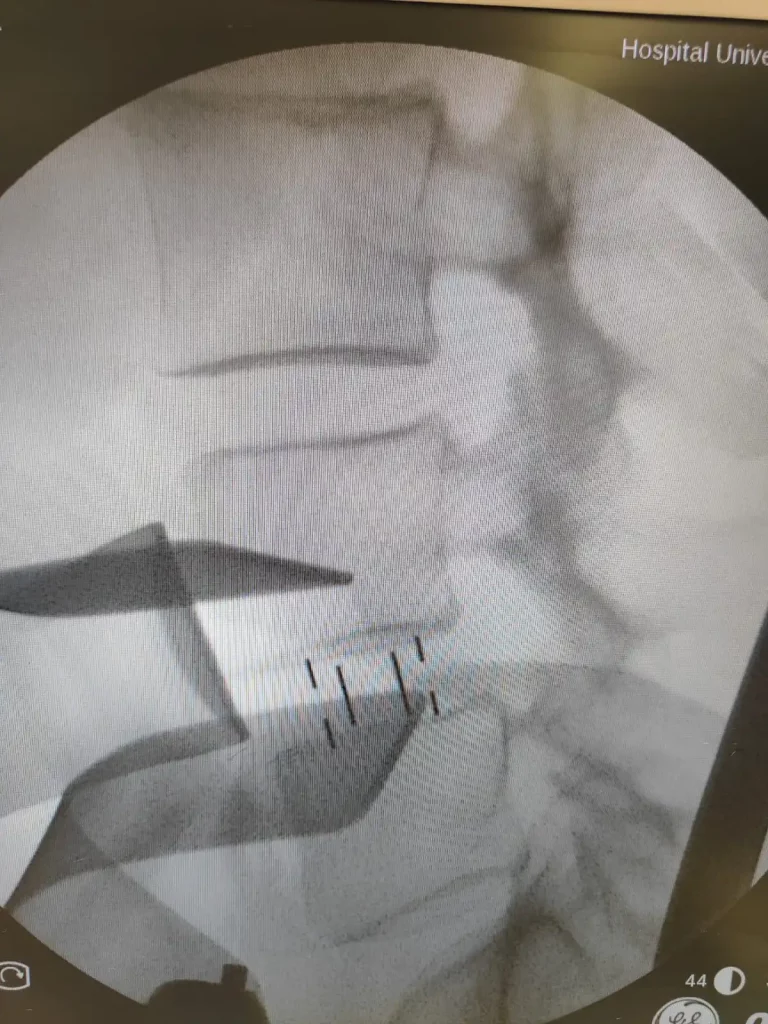

La XLIF (Extreme Lateral Interbody Fusion) es una cirugía de fusión lumbar que llega al disco intervertebral desde el lado del cuerpo. En lugar de entrar por la espalda con una disección muscular amplia, el acceso es lateral, atravesando el músculo psoas. El objetivo principal es colocar un implante (una “caja” o separador) entre dos vértebras para recuperar altura, mejorar alineación y crear un entorno estable para que el hueso consolide (fusión).

• Imagen: resonancia para nervios y discos; radiografías de pie para alineación y listesis; en algunos casos TAC para hueso o para planificar.